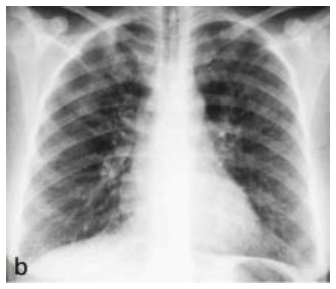

Analise a imagem abaixo para responder à questão.

É correto afirmar que a radiografia acima demonstra